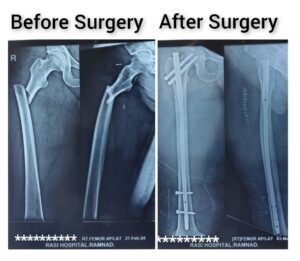

Dr.Nazar Ali MBBS ; D.ORTHO is a distinguished Orthopedic and Trauma Surgeon with specialized expertise in joint replacement, arthroscopy, sports injuries, and complex trauma care. With a strong academic background and years of dedicated clinical practice, Dr.Nazar ali has established himself as a trusted name in advanced orthopedic care.

He is proficient in performing a wide range of orthopedic procedures, including robotic and minimally invasive joint replacement surgeries, arthroscopic ligament reconstructions, deformity corrections, and complex fracture management. His surgical approach is complemented by a deep commitment to patient-centered care, ensuring that every treatment plan is tailored to the individual needs of his patients.

Dr.JAMEER ALI MBBS;D.Ortho;DND (Ortho) is a highly skilled Orthopedic and Trauma Surgeon specializing in joint replacement, arthroscopy, and complex fracture management. With extensive training and clinical experience, Dr.Jameer ali is committed to providing comprehensive musculoskeletal care through advanced surgical techniques and patient-centered treatment. Passionate about innovation in orthopedics, he emphasizes minimally invasive approaches, rapid recovery protocols, and evidence-based practices. Known for his precision, compassion, and dedication, Dr.Jameer ali has successfully treated a wide spectrum of orthopedic conditions, restoring mobility and improving quality of life for countless patients.